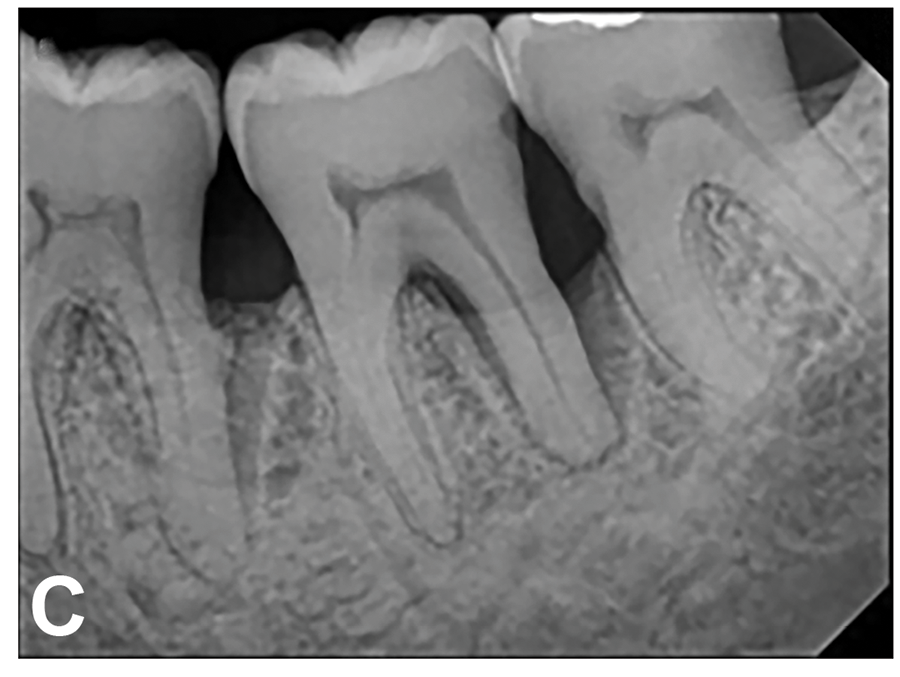

(7.) Progressive improvement in bone quality, quantity, and morphology during each time period, especially in the furcation area of tooth No. 18, which shows a noticeable narrowing of the width of the bony defects, slight apical resorption of the distal root of tooth No. 18, and the encasing of residual cementum on the distal root of No. 19 by new bone formation. Periapical radiographs were taken of teeth Nos. 17, 18, and 19 on June 25, 2016, January 28, 2017, August 23, 2019, and September 4, 2020, respectively, the final of which was taken after almost 5 years post-initial scaling and root planing and alternating supportive periodontal maintenance.

Figure 7

(8.) Progressive improvement in bone quality, quantity, and morphology during each time period, especially in the furcation area of tooth No. 18, which shows a noticeable narrowing of the width of the bony defects, slight apical resorption of the distal root of tooth No. 18, and the encasing of residual cementum on the distal root of No. 19 by new bone formation. Periapical radiographs were taken of teeth Nos. 17, 18, and 19 on June 25, 2016, January 28, 2017, August 23, 2019, and September 4, 2020, respectively, the final of which was taken after almost 5 years post-initial scaling and root planing and alternating supportive periodontal maintenance.

Figure 8

(9.) Progressive improvement in bone quality, quantity, and morphology during each time period, especially in the furcation area of tooth No. 18, which shows a noticeable narrowing of the width of the bony defects, slight apical resorption of the distal root of tooth No. 18, and the encasing of residual cementum on the distal root of No. 19 by new bone formation. Periapical radiographs were taken of teeth Nos. 17, 18, and 19 on June 25, 2016, January 28, 2017, August 23, 2019, and September 4, 2020, respectively, the final of which was taken after almost 5 years post-initial scaling and root planing and alternating supportive periodontal maintenance.

Figure 9

(10.) Progressive improvement in bone quality, quantity, and morphology during each time period, especially in the furcation area of tooth No. 18, which shows a noticeable narrowing of the width of the bony defects, slight apical resorption of the distal root of tooth No. 18, and the encasing of residual cementum on the distal root of No. 19 by new bone formation. Periapical radiographs were taken of teeth Nos. 17, 18, and 19 on June 25, 2016, January 28, 2017, August 23, 2019, and September 4, 2020, respectively, the final of which was taken after almost 5 years post-initial scaling and root planing and alternating supportive periodontal maintenance.

Figure 10

(12.) Follow-up radiographs taken of teeth Nos. 17, 18, and 19 on September 4, 2020 after almost 5 years post-initial scaling and root planing and alternating supportive periodontal maintenance therapy only.

Figure 12

(13.) Follow-up radiographs taken of teeth Nos. 17, 18, and 19 on September 4, 2020 after almost 5 years post-initial scaling and root planing and alternating supportive periodontal maintenance therapy only.

Figure 13

The patient's periodontal disease improved with initial nonsurgical periodontal therapy that involved scaling and root planing. This initial treatment was followed by only SPT every 3 months. Despite treatment, residual deep periodontal probing depths remained, so a decision was made to maximize improvements with nonsurgical therapy and to reassess as needed to determine whether surgical intervention was appropriate. After almost 5 years of SPT and good patient compliance with plaque control and supportive care, the periodontium was stable. Because of the resulting bone formation and improvements in clinical attachment levels (Figure 7 through Figure 13), it was determined that periodontal surgical intervention was not necessary.

Although rare, the radiographic evidence in the current case indicated that nonsurgical therapy effectively halted the destructive effects of severe chronic periodontitis and led to bone regeneration, thereby eliminating the need for surgery. The current case also showed that nonsurgical periodontal therapy may lead to desirable outcomes for patients with severe chronic periodontal disease if the patient is compliant with plaque control, supportive periodontal therapy is provided, etiological and risk factors are eliminated, and the body is given adequate time to heal.11 An additional factor that may have influenced the positive outcome of the current case was the patient's favorable health status.